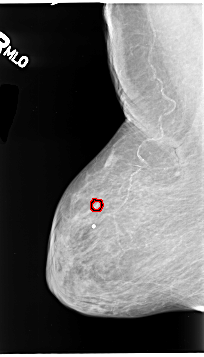

B_3130_1.RIGHT_MLO

RIGHT_MLO LINES 4632 PIXELS_PER_LINE 2640 BITS_PER_PIXEL 12 RESOLUTION 50 OVERLAY

FILE: B_3130_1.RIGHT_MLO.OVERLAY

TOTAL_ABNORMALITIES 1

ABNORMALITY 1

LESION_TYPE CALCIFICATION TYPE PLEOMORPHIC DISTRIBUTION CLUSTERED

ASSESSMENT 4

SUBTLETY 3

PATHOLOGY BENIGN

TOTAL_OUTLINES 1

BOUNDARY